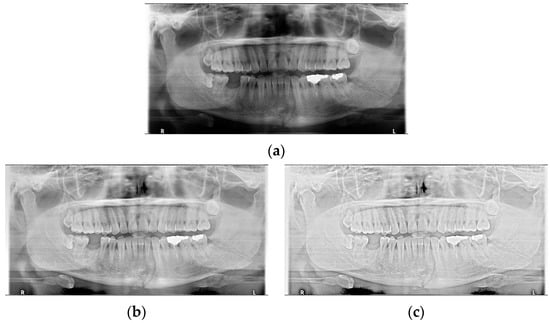

For the case of Figure 12 images, it is possible to check the amount of local contrast improvement from the line profile information. In order to compare the changes in pixel brightness near angle fracture in the normal, SLAT and MLAT panoramic radiographs, the result of line profiles are shown in Figure 14 and Table 7. When comparing the maximum pixel brightness, minimum pixel brightness, average pixel brightness, and standard deviation in the line profile of the straight arrow near the angle fracture site, the normal panoramic radiograph has the largest standard deviation value of 5.6. Due to the characteristics of LAT processing, a dark area increases contrast, but as it becomes a bright area, contrast is maintained or slightly lowered.

Figure 14.

The comparison of SLAT and MLAT processing with line profiler: (a) normal radiograph, (b) SLAT-processed, and (c) MLAT-processed.

However, except for some bright radiograph images, the effect of LAT processing is evident in most dark radiograph images. As shown in Figure 15, most of the LAT-processed radiographs have a high standard deviation value compared to the normal radiographs. In Table 7, the LAT-processed panoramic radiographs shows the higher deviation values of 14.6 and 15.2, which are reasonably more than 9.3 of the normal panoramic radiograph.

Figure 15.

The comparison of SLAT and MLAT processing with line profiler: (a) normal radiograph, (b) SLAT processed, and (c) MLAT processed.